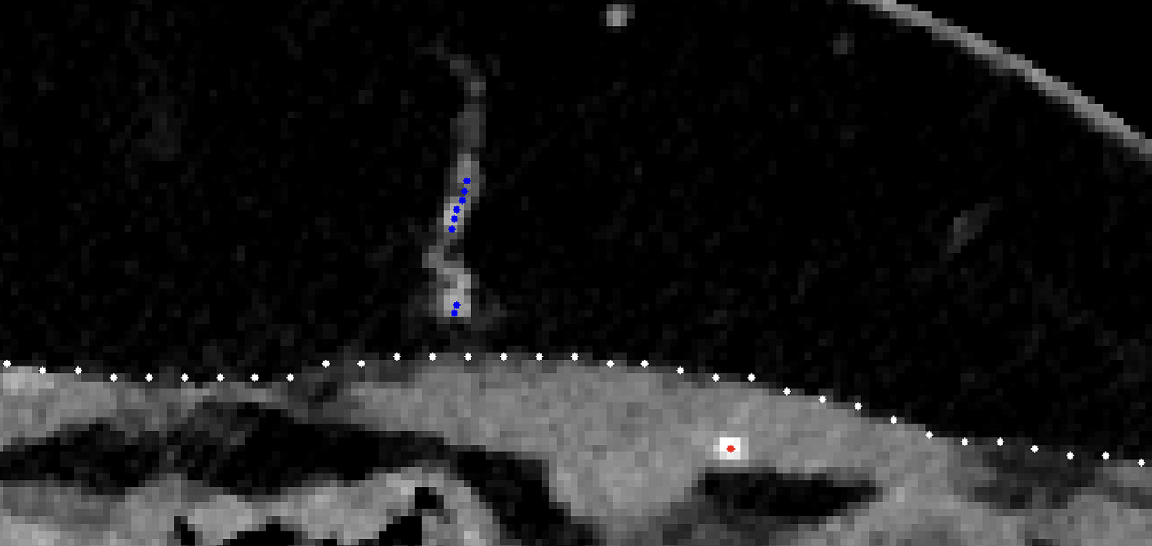

Anonymized images were blindly analysed by the engineering team using a divide-and-conquer methodology [9], combining a tracking procedure and a minimum cost approach (Figs. 2 and 3). A map report was produced at the end of the process, reporting the same features of the manual identification: calibre, orientation and distance to the umbilicus (horizontally and vertically).

The tracking procedure extracts the subcutaneous course of a perforator, from a point near its end to the location where it leaves the rectus abdominis fascia. The minimum cost approach finds the intramuscular path from this last point to the location where the artery perforates the posterior lamella of the rectus abdominis muscle. The process lasts around 30 min (mostly due to the time spent loading the data and selecting the few points required).

Fig. 7. Localization estimated by the software in comparison with the manual report.

Regarding the software estimates of where the perforators leave the fascia, horizontal error was not statistically significant, P ≈ 0.09 (170º of freedom), and the effect size was small, r = 0.13. However, vertical error was statistically significant, P ≈ 0.02 (170º of freedom), but the effect size was also small, r = 0.18. Fig. 7 shows a representation of the software localization estimates according to the manual reference. Regarding error in height, the average absolute error was 3.2 ± 2.4 mm, whereas the horizontal average absolute error was 2.5 ± 2.0 mm.